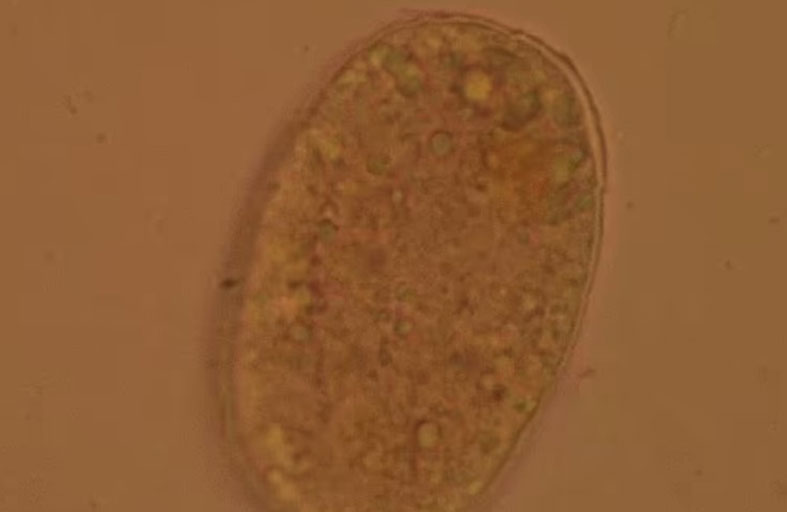

أطباء يصورون ديداناً مصاصة للدماء في أمعاء امرأة

أظهرت صور لحظة اكتشاف الأطباء لديدان تمتص الدماء تتلوى في أمعاء امرأة صينية، وكانت المزارعة البالغة من العمر 75 عاماً تعاني من مشاكل النوم وضعف الشهية والدوار لمدة شهرين قبل أن تسعى أخيراً للحصول على مساعدة طبية، وبعد حضورها إلى المستشفى، كشفت فحوصات الدم أنها تعاني من فقر دم حاد، وفقاً للأطباء الصينيين الذين شاركوا قصتها في إحدى المجلات.

وبحسب "دايلي ميل" عرض الأطباء في البداية على المرأة علاجات بسيطة، ولكن عندما استمرت المشاكل، أجرى الأطباء تنظيراً داخلياً، بإدخال كاميرا في الأمعاء عبر الفم، ووجدوا ديداناً خطافية حية تزحف في أمعائها.

وأظهرت الاختبارات أيضاً أن بيض الديدان الخطافية في برازها كان من نوع necator americanus، وهو نوع معروف بأنه يسبب فقر دم حاداً، حيث تتغذى هذه الطفيليات على الدم في الأمعاء، مما قد يؤدي إلى نقص حاد في الحديد بمرور الوقت.

وقال الأطباء في جامعة سنترال ساوث في هونان إن المرأة - التي لم يتم تحديد هويتها - ربما تعرضت للديدان من خلال التربة الملوثة أثناء عملها كمزارعة.

وعلى الرغم من أن الإصابة بالدودة الخطافية مسألة نادرة في الصين، إلا أنها تظل مصدر قلق في المناطق الريفية، حيث قد لا يزال انتشار مثل هذه العدوى أكثر من تقديراته.